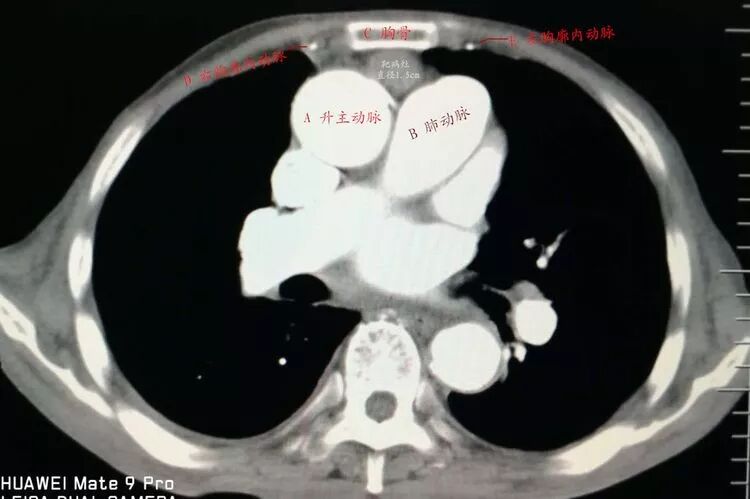

增強掃描顯示病灶與大血管關系密切!難度大、風險高!但沒有其它檢查手段或設備可替代穿刺活檢。

前有胸骨C,后有主肺動脈A、B,兩側有胸廓內動脈D、E遮擋,形成合圍之勢。